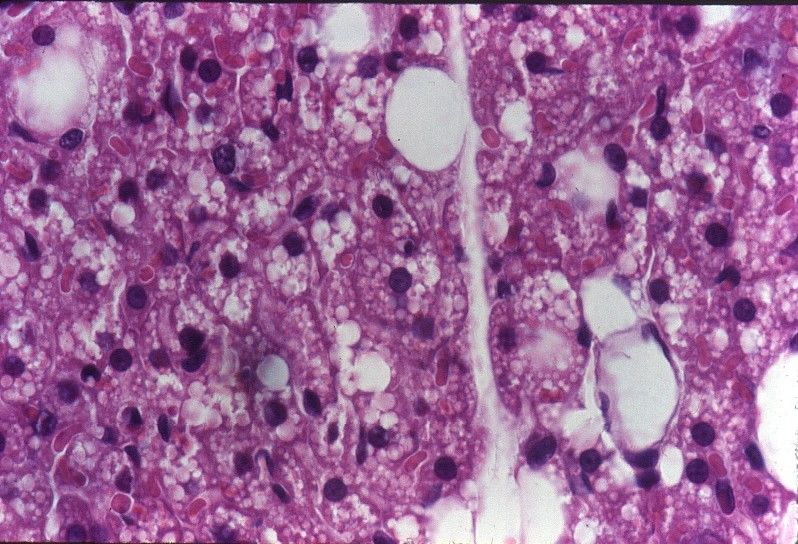

1. Tejido adiposo

2. Blanco

1. Almacena energía

1. Fagocitosis

2. Estirpes celulares del tejido adiposo

1. Macrófagos